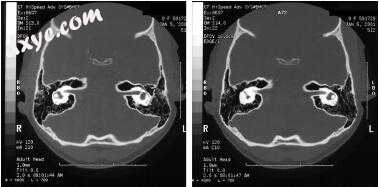

图-8. 通过前庭迷路细胞束(A)和后半规管(B)进行岩尖顶气化。 (From Harker LA: Cranial and intracranial complications of acute and chronic otitis media. In Snow JB, Ballenger JJ, editors: Ballenger’s otorhinolaryngology head and neck surgery, ed 16, Hamilton, Ontario, 2003, Decker.)

图-9. 通过反迷路神经细胞束在两层内听道和前庭的石蕊顶点气化。 (From Harker LA: Cranial and intracranial complications of acute and chronic otitis media. In Snow JB, Ballenger JJ, editors: Ballenger’s otorhinolaryngology head and neck surgery, ed 16, Hamilton, Ontario, 2003, Decker.)

图-10. 在内耳道水平通过右颞骨中的迷走神经细胞束进行岩尖顶气化。 (From Harker LA: Cranial and intracranial complications of acute and chronic otitis media. In Snow JB, Ballenger JJ, editors: Ballenger’s otorhinolaryngology head and neck surgery, ed 16, Hamilton, Ontario, 2003, Decker.)